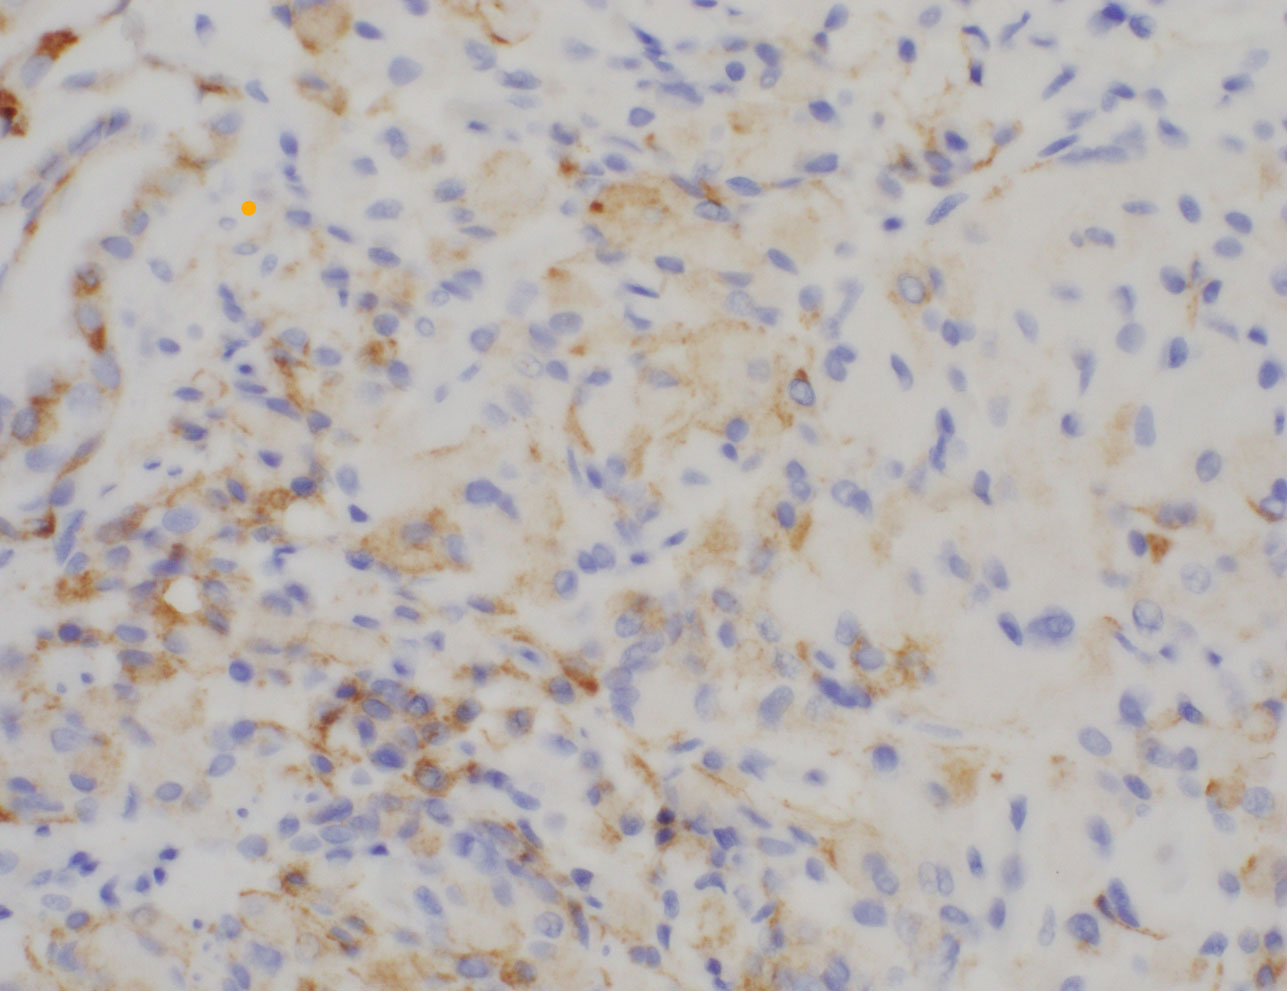

Screening colonoscopy demonstrated multiple polyps in the transverse colon and one diminutive (5 mm) polyp in the sigmoid colon. Histologically, the sigmoid polyp showed a hyperplastic polyp with an associated expansion of the lamina propria by a vaguely nodular proliferation of epithelioid cells. The epithelioid cells were arranged in small clusters with round nuclei, eosinophilic cytoplasm, and occasional nuclear grooves (Figures A-C). There was no cytologic atypia, mitotic activity, or necrosis. The epithelioid cells were positive for EMA (weak diffuse expression, figure D), while they were negative for pankeratin, GLUT1, S-100, SOX10, HMB45, DOG1, ERG, CD68, CD163, and SMA.